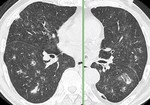

[画像診断]Wegener肉芽腫症の胸部CT所見について 2010-09-11